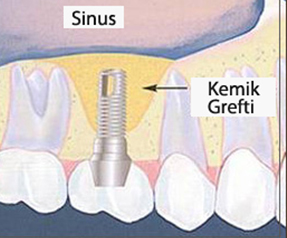

SİNÜS LIFTING VE ALVEOL KEMİĞİ OPERASYONU

DETAYLI BİLGİ